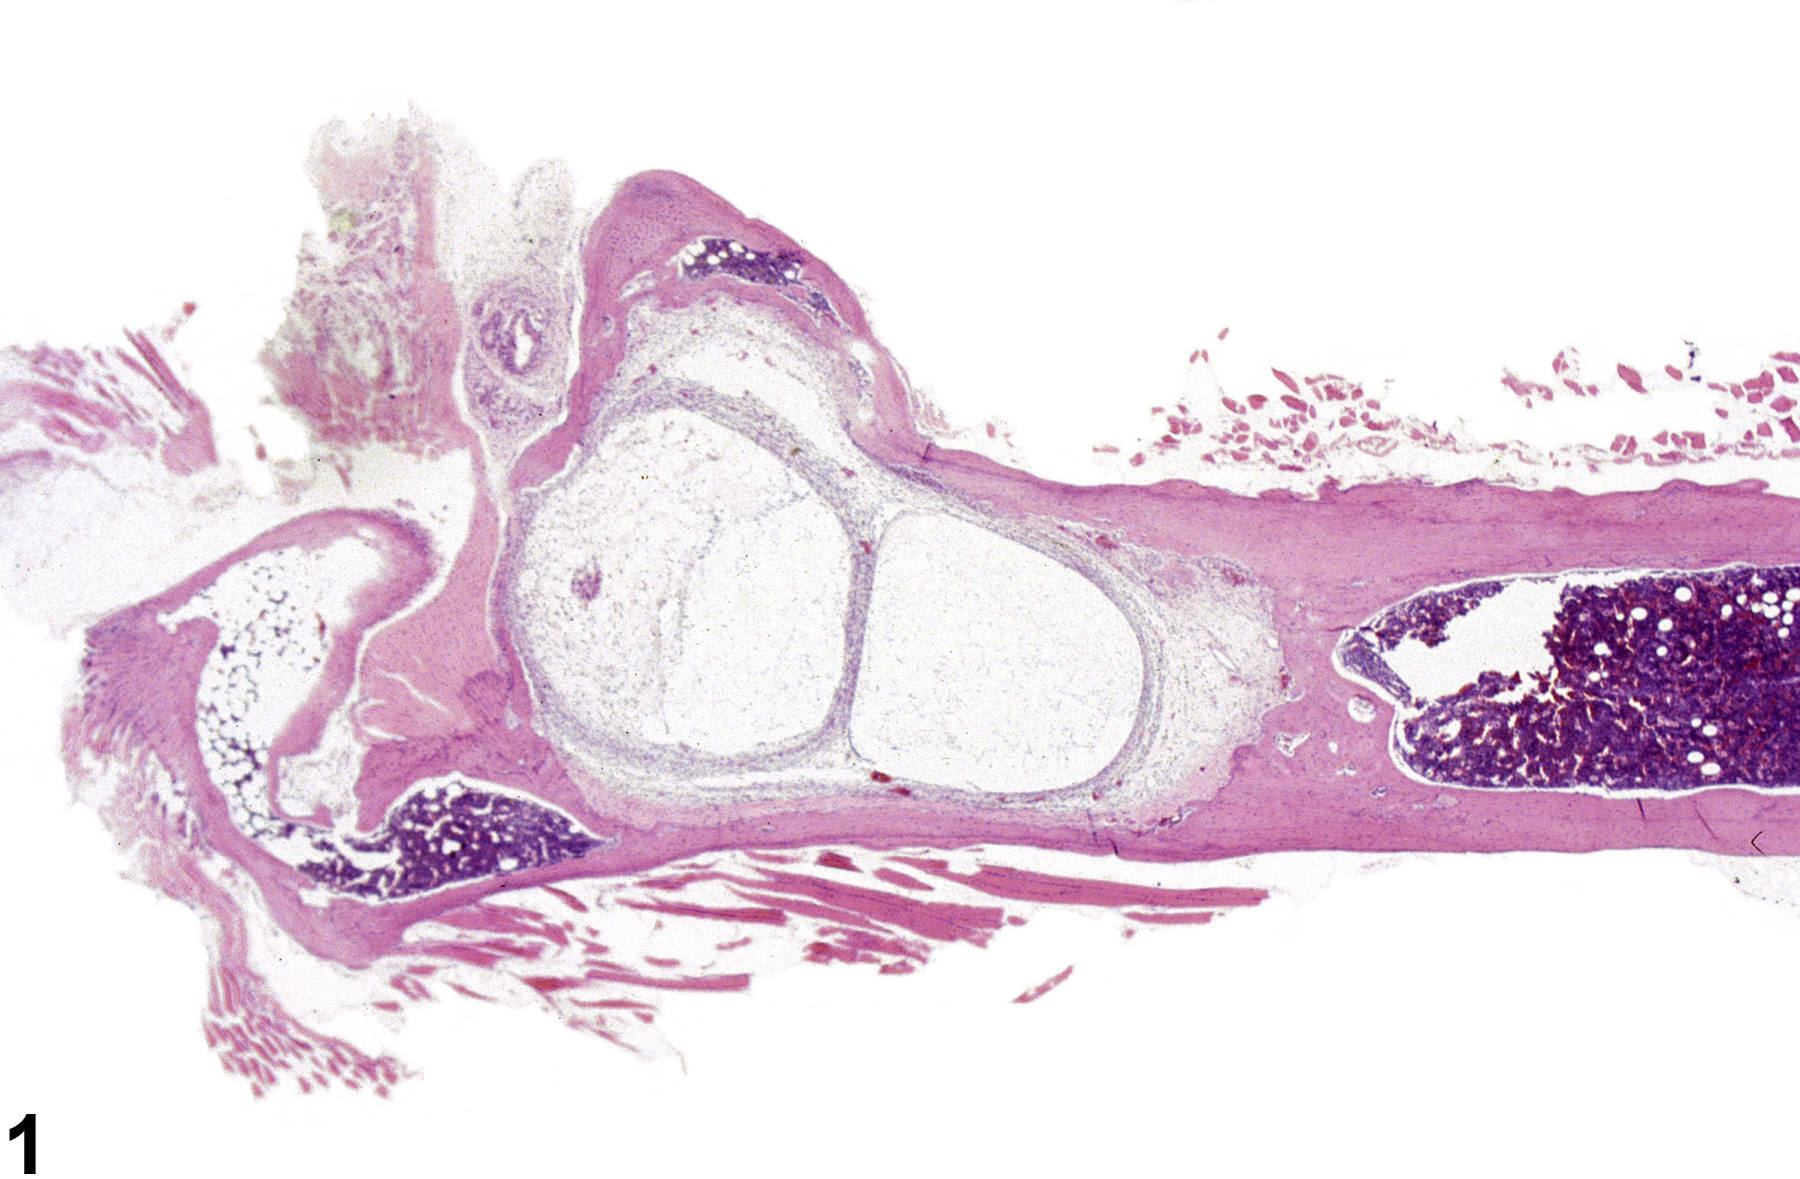

Гистологические изображения фолликулярной кисты яичника